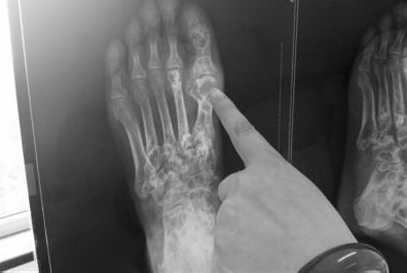

王怀庆医生替段先生做了详细的检查,由于段先生平时喜欢吃大鱼大肉,鲍参翅肚,体内尿酸浓度很高,通过X片显示,段先生的大脚趾关节形成多颗珍珠大的痛风石,情况不是很乐观。王怀庆医生建议进行“中医微创可视针刀镜技术”科学诊疗方案治疗。

(图:段先生的X光片显示,其左脚大拇指处痛风石较为严重)